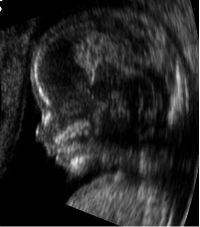

- متابعة وتصوير الجنين أثناء فترة الحمل.

| طب التوليد | Obstetrical sonography is commonly used during pregnancy to check on the development of the fetus. | انظر obstetric ultrasonography |